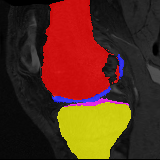

Image Manual Seg DA-1 Mono-5 DA-5 Mono-200 Refer to caption Refer to caption Refer to caption Refer to caption Refer to caption Refer to caption

Figure 4: Examples of brain MRI registration (top) and knee MRI segmentation (bottom) results. Top: The first two columns are the moving image/segmentation and the target image/segmentation followed by the warped moving images/segmentations by different models. Bottom left to right: original image, manual segmentation, and predictions of various models. Mono-i𝑖i and DA-i𝑖i represent the mono- and DA models trained with i𝑖i manual segmentations respectively.

Results: All trained networks are evaluated using Dice overlap scores between predictions and the manual segmentations for the segmentation network, or between the warped moving segmentations and the target segmentations for the registration network. Tabs. 1 and 2 show results for the knee and brain MRI experiments respectively in Dice scores (%). Fig. 2 shows examples of knee MRI registrations and brain MRI segmentations.

Knee results: On knee MRIs, our method improves segmentation scores over separately learned networks by about 1.2 and 0.5, and registration scores increase by about 3.1 and 3.0, when training with 5 and 10 manual segmentation respectively. Especially for the challenging cartilage structures, our joint learning boosts segmentation by 1.4 and 0.7, and registration by 5.5 and 5.2 for N=5 and N=10 respectively.